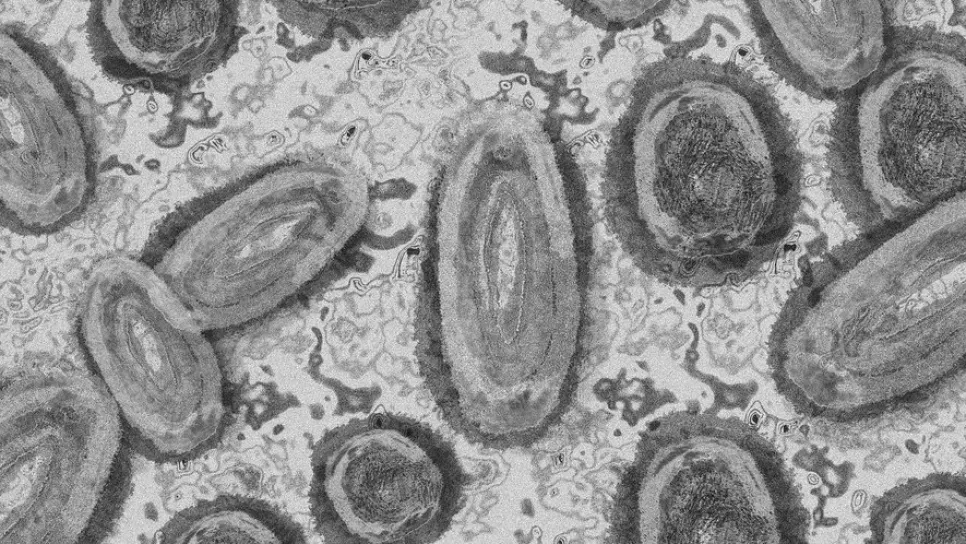

قال المدير العام لمنظمة الصحة العالمية تيدروس أدهانوم غيبريسوس، إن عدد الأشخاص الذين تم تشخيص إصابتهم بجدري القرود في ظل التفشي الحالي تجاوز 3200 شخص. وقال غيبريسوس يوم الخميس، مخاطبا لجنة الطوارئ للوائح الصحية الدولية فيما يتعلق بتفشي جدري القرود الحالي: "قبل ما يزيد قليلا عن ستة أسابيع، تم إخطار منظمة الصحة العالمية بمجموعة عائلية من ثلاث حالات من جدري القرود دون أي سفر حديث خارج المملكة المتحدة". وأضاف: "منذ ذلك الحين، تم الإبلاغ عن أكثر من 3200 حالة مؤكدة من جدري القرود، ووفاة واحدة، إلى منظمة الصحة العالمية، من 48 دولة بما في ذلك نيجيريا، وفي خمسة أقاليم لمنظمة الصحة العالمية". ووفقا لر...